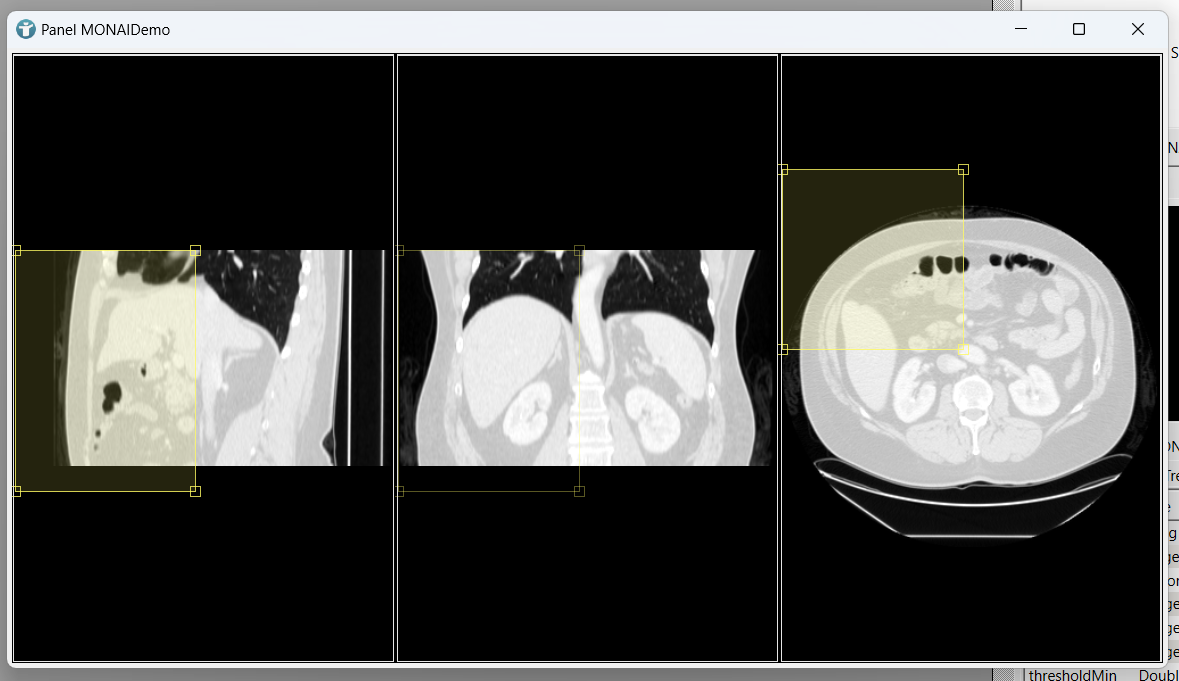

If you now open the panel of our MONAIDemo module, we can manually move the box in all three dimensions.

Execute the Segmentation

If you now load an image using the itkImageFileReader module, you can manually adapt your bounding box to include the spleen and start segmentation.

The results are shown as a semitransparent overlay.